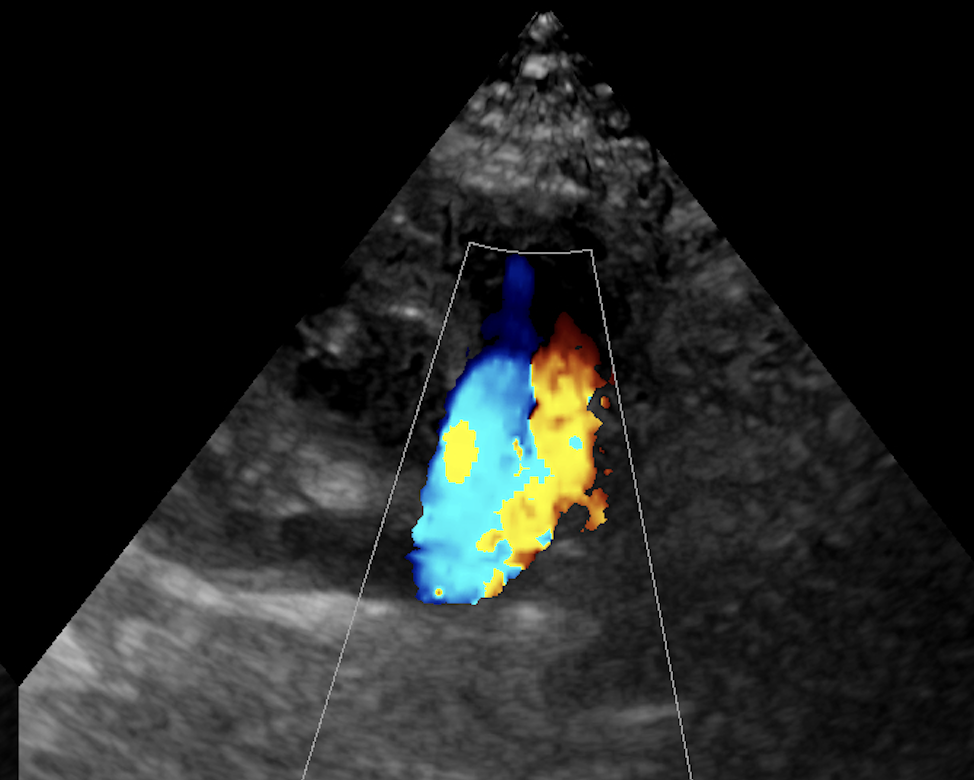

PDAの確定診断は心エコー検査が必要ですが、超音波を当てれば比較的簡単に診断できます。超音波検査で下行大動脈から左肺動脈へと向かう短絡血流を確認することが必要です。

手術後には逆流がなくなっている。

病気が確定出来たら検査時点での病状の状態を把握する必要があるため、レントゲンや心電図、血液検査などを含めた心機能検査をして手術の予定を決めます。心機能検査のための超音波はとても重要でこれは血液の流速や、動脈管の太さなどなるべく正確に知りたいので多少の技術が必要です。その血流波形を確認して最大血流速度が3.5m/sec以下の場合は、肺高血圧症の合併症も疑わなければならないため、検査による描出と計測はとても重要です。